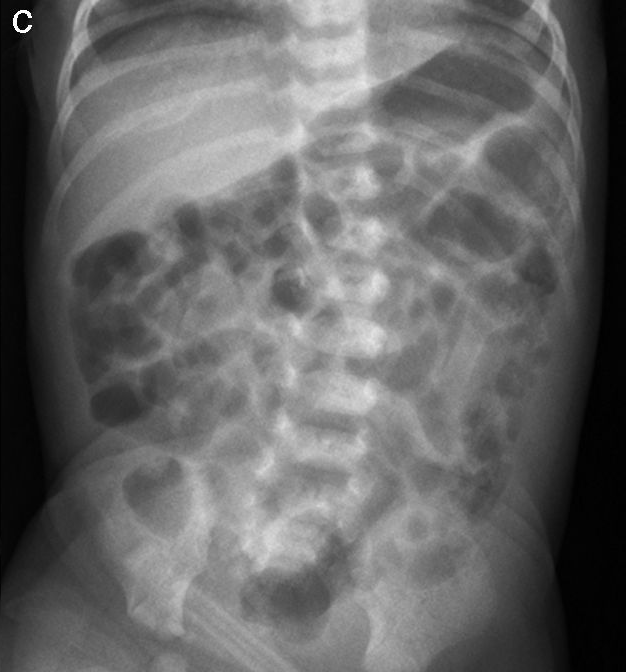

En neonatos, la obstrucción intestinal puede ser diagnosticada mediante una serie de hallazgos radiológicos característicos. La evaluación radiológica es crucial para diferenciar entre las diversas causas de obstrucción intestinal, que pueden ser de origen alto o bajo, y para determinar el manejo adecuado.

1. Radiografía Abdominal: Es la primera línea de imagen utilizada para evaluar la obstrucción intestinal en neonatos. Los hallazgos típicos incluyen dilatación de asas intestinales y la presencia o ausencia de niveles hidroaéreos, lo cual puede indicar si la obstrucción es proximal o distal. Por ejemplo, la «burbuja única» se asocia con atresia esofágica, la «doble burbuja» con atresia duodenal, y la «triple burbuja» con atresia yeyunal.[1-2]